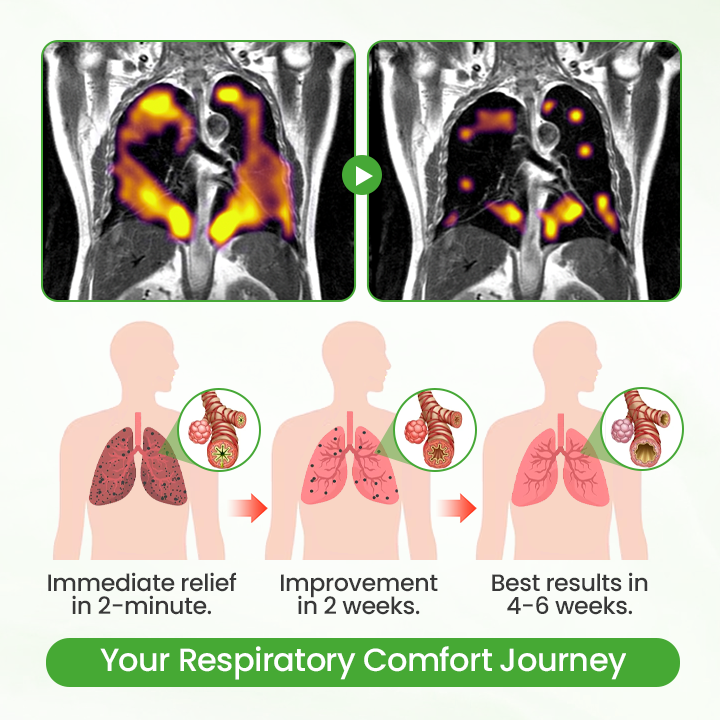

Your Respiratory Comfort Journey: What to Expect

Unlike traditional supplements that take hours to work, Qooes® Breatheora delivers a clear comfort timeline. Within 2 minutes, you'll feel significant soothing relief as mullein extract makes direct contact with your respiratory tissues. After 2 weeks of consistent use, persistent coughing and chest tightness begin to fade noticeably. By 4 weeks, you'll experience sustained respiratory comfort improvement - breathing freely again. This progressive support works with your body's natural processes for long-term wellness, not just temporary relief.

Real-World User Study Results

94.2% of users felt immediate relief within 2 minutes of first use, far faster than oral supplements

89.7% of users breathed significantly smoother within 2 minutes after use, and the feeling of chest tightness and breathlessness disappeared

91.8% of users had a significant reduction in cough after 4-8 weeks of continuous use, and most of the chronic cough disappeared completely

96.1% of users believe that nasal inhalation is more effective than all oral supplements and are reluctant to return to traditional products